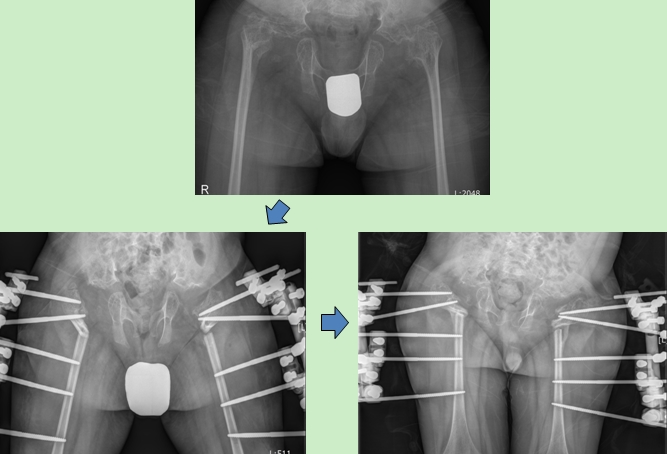

공지 척추골단이형성증 환자의 고관절 교정

척추골단이형성증 환자로 보행이 불편하고 척추기 휘어 고관절 교정술을 시행하였습니다.

Hip joint correction was performed on the patient with spondyloepiphyseal dysplasia due to difficulties in walking and deformed spine.